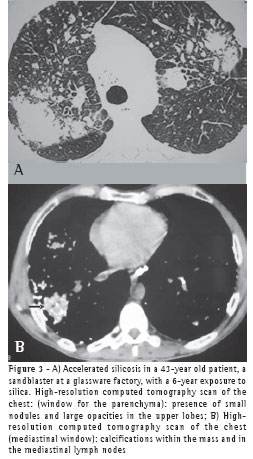

Of the 75 PMF patients, 44 underwent chest HRCT. The HRCT scans revealed that 88.6% of the masses were located in the upper thirds of the lungs and were posterior. Cavitations were observed in 18.18% of the masses, air bronchogram in 70.4% and internal calcification in 63.6%. Emphysematous lesions surrounding the masses were observed in 72.7%, and lymph node calcification was seen in 81.8% (Figures 3A and 3B).

In the present study, chest HRCTs revealed that the large opacities were predominantly (in 88.6% of the cases) located in the upper and posterior thirds of the lung.Air bronchograms and calcifications within the masses were found in over half of the patients. Calcified hilar and mediastinal lymph nodes were observed in 81% of the cases, 25% being of the eggshell type. Only 8 cases displayed cavitation within the masses, 6 presenting concomitant tuberculosis.

Some authors(20) have described sparse calcifications within silicosis-related PMF masses, whereas others(21) have reported lymph node calcification in 26 of 49 silicosis cases studied, 12.2% being of the eggshell type, which was found to be much more frequent in accelerated silicosis than in the simple nodular form.